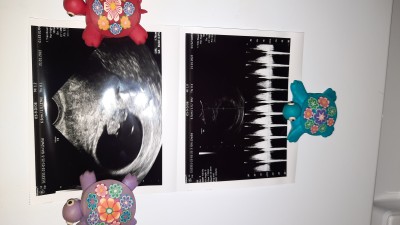

Bayanlar ilk gebeliğim olduğu için merak ediyorum ..Resim ekliyorum acaba burada boy kilo yaziyor mu ?? :)

Gebelik haftası 8+4

Baş popo mesafesi yazar crl olarak ama okunmuyor

Evet crl 1.76 yaziyor

Tamam 1,76 cm miş baş popo mesafesi uzunca bir süre başpopo mesafesi ölçülcek boyu sonra kilosuda

Crl 1.76 ise daha iki cm bile degil demektir bu :) kilosu da 14-15. Haftadan snra olculmeye baslaniyor :))